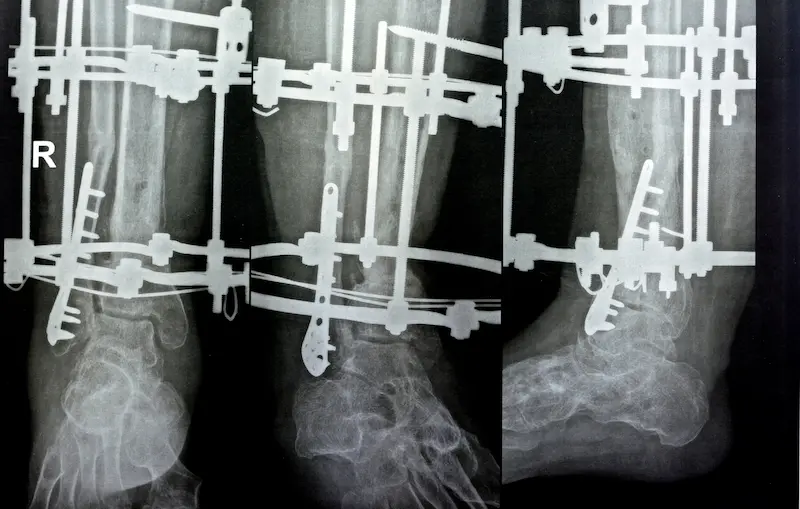

ظهر جهاز إليزاروف لأول مرة في الخمسينيات من القرن الماضي على يد الجرّاح الروسي جافريل إليزاروف، كأحد الحلول لعلاج الكسور الصعبة والتشوّهات الخلقية أو المكتسبة في العظام. تقوم فكرته على استخدام حلقات معدنية يتم توصيلها بالجزء الخارجي من الطرف (الذراع أو الساق) عبر أسلاكٍ أو دبابيس معدنية تخترق العظم من جهات مختلفة. وبفضل ضبط المسافات والثبات بين تلك الحلقات والأسلاك، يمكن للطبيب تحقيق التثبيت العظمي، أو حتى إليزاروف لتمديد الأطراف بشكل تدريجي. وقد أثبت نجاحًا ملحوظًا في توحيد العظام المكسورة وتعويض الفقد العظمي، وتصحيح الاعوجاجات. إن الفلسفة وراء هذه التقنية تتمحور حول قدرة العظم البشري على التجدد والنمو عندما تتوفر له الظروف الميكانيكية والحيوية الملائمة. واستنادًا إلى ذلك، تمّ تطوير الجهاز ليكون قاعدةً مثاليةً في حالاتٍ مثل تطويل العظام أو تعديل التشوهات القُطرية أو الطولية. بات جهاز إليزاروف ينتشر على نطاق أوسع مع تتالي النجاحات والاعتراف الدولي بجدواه، وتطور تصميمه عبر الزمن ليصبح أخفّ وأسهل في الاستخدام، وأكثر دقة.

يعتمد الجهاز على مبدأ “الإلهاء” (Distraction) أو السحب التدريجي للعظام في الحالات التي تتطلب تمديدًا أو تصحيحًا، وأيضًا على مبدأ “التثبيت المستقر” (Stable Fixation) في حالات الكسور الحادة أو المفتوحة. يُثبت الجهاز خارج جلد المريض، ويُربط عبر أسلاك معدنية أو مسامير رفيعة تخترق العظم بشكل مدروس ومحسوب.

- في حالة الإلهاء: يقوم الطبيب بضبط البراغي المفصلية لخلق شد بسيط بين نهايات العظم بشكلٍ يومي، ما يسمح بتحفيز عظام جديدة للنمو في الفراغ الناتج بين الطرفين. وبهذا، يمكن زيادة الطول بضعة ميلليمترات يوميًا، وصولًا إلى الطول المطلوب.

- في حالة التثبيت: يُستخدم الجهاز للحفاظ على ثبات الكسر في الوضع الصحيح، مع الحفاظ على مسافات وأسلاك تضمن عدم حركة قطع العظم خلال فترة الالتئام. وهذا يسمح للأنسجة بالالتئام بطريقة آمنة دون أن تتعارض قوى الضغط أو الشد.